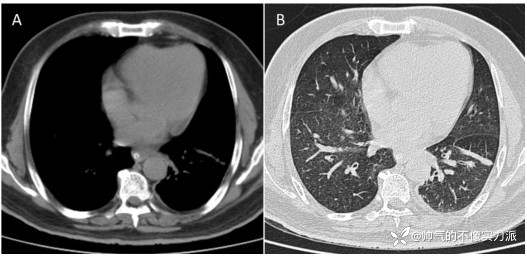

患者开始接受全身皮质类固醇治疗和口服伊曲康唑治疗。通过药物治疗,全身感觉功能逐渐改善,支气管痉挛持续改善,5天后他停止了IMV。在接下来的几天里,他被转移出重症监护室,并开始接受康复治疗。此时进行的胸部高分辨率CT扫描显示左肺下叶线性肺不张(图2)。

图2 胸部高分辨率CT

(A)纵隔窗和(B)肺窗,(A)和(B)均显示左肺下叶线性肺不张